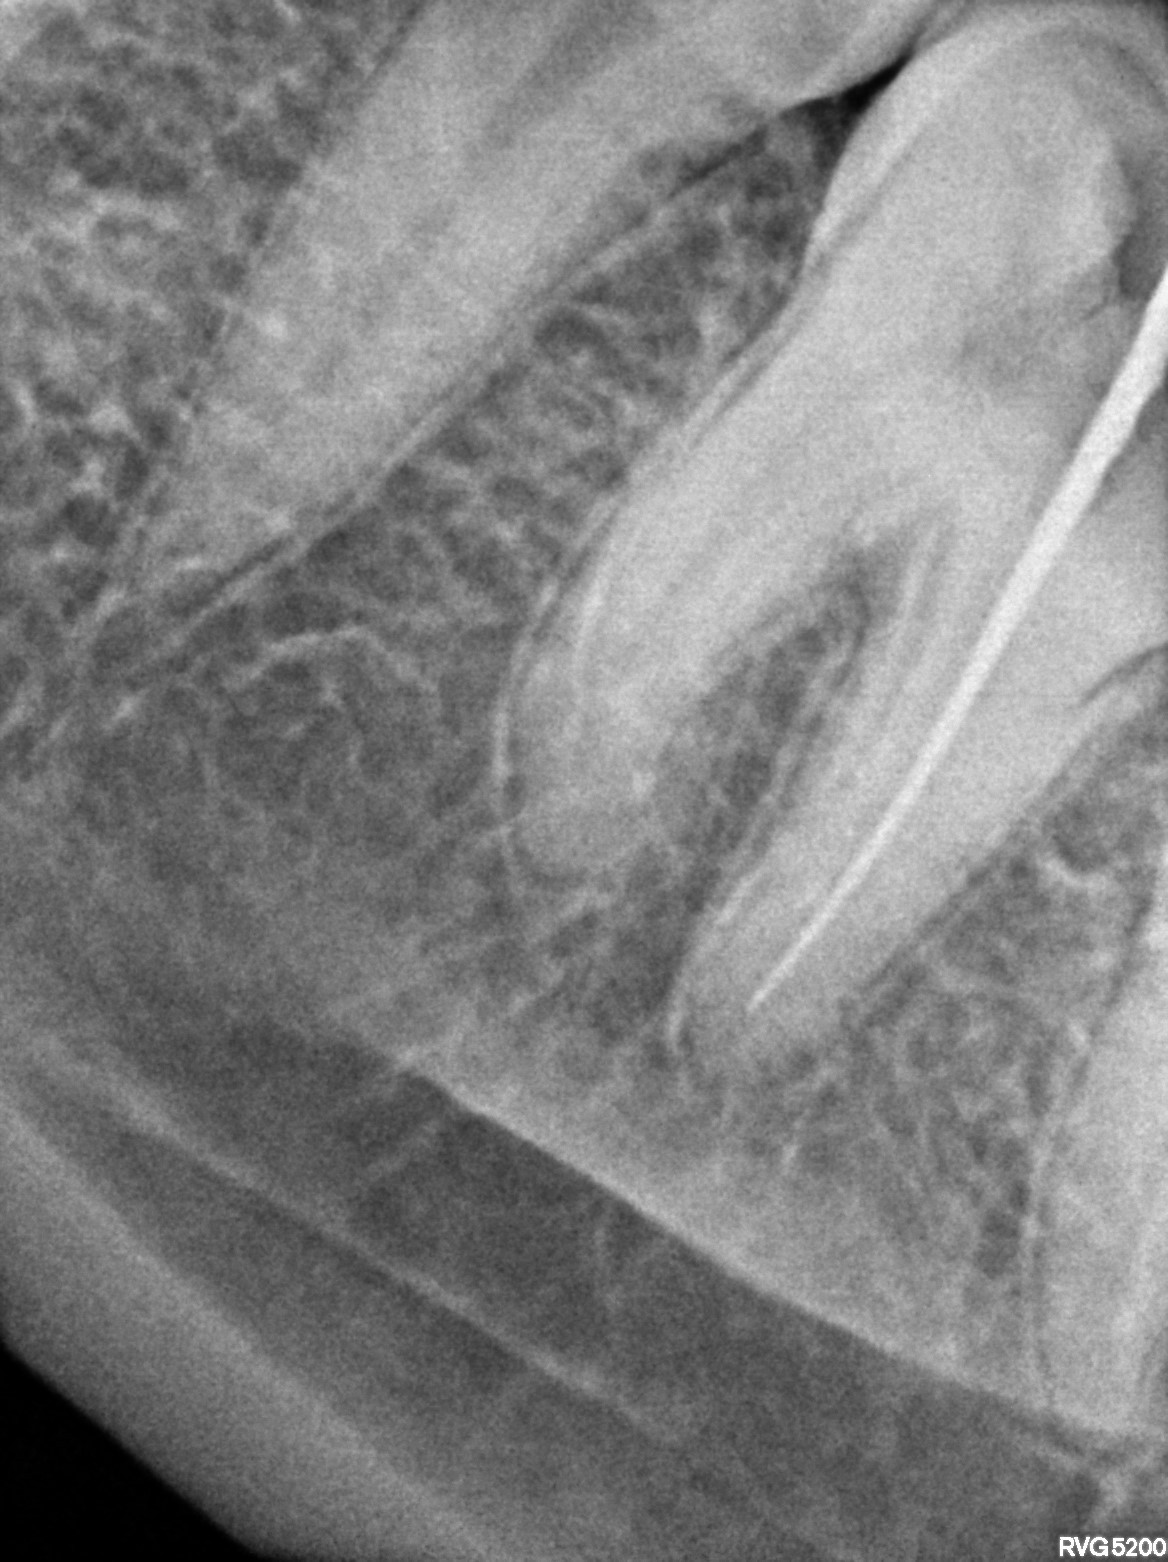

Dental Radiographs FHIR: DocumentReference · LOINC 24641-7

xray_1772613108_3.jpg

24641-7